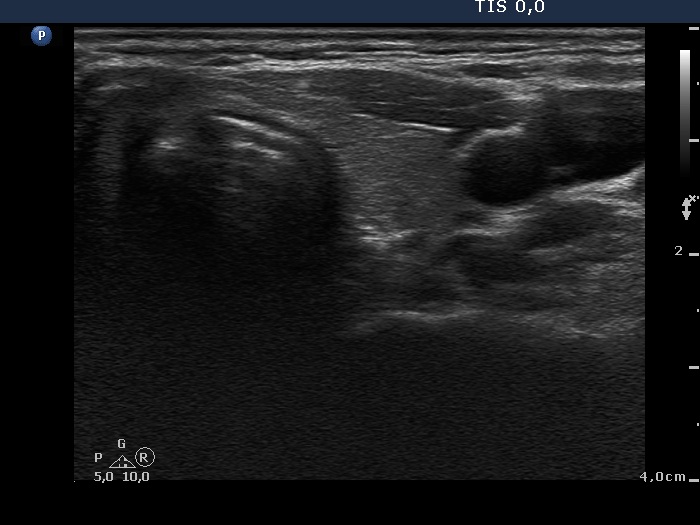

Discrete lesion or nodule in Hashimoto's thyroiditis - case 26 (1048) (ultrasonographic picture 5)

Left lobe, transverse scan. This lobe is minimally hypoechogenic.